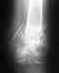

úÄÒÁ×ÓÔ×ÕÊÔÅ! 18 ÉÀÎÑ × ÒÅÚÕÌØÔÁÔÅ äôð ÐÏÌÕÞÉÌÁ ÔÒÁ×ÍÙ: ÔÕÐÕÀ ÔÒÁ×ÍÕ ÖÉ×ÏÔÁ,ÒÁÚÒÙ× ÓÅÌÅÚÅÎËÉ, ÍÎÏÖÅÓÔ×ÅÎÎÙÅ ÐÅÒÅÌÏÍÙ ËÏÓÔÅÊ ÔÁÚÁ, ËÏÍÐÒÅÓÓÉÏÎÎÙÊ ÏÓËÏÌØÞÁÔÙÊ ÐÅÒÅÌÏÍ ÔÅÌ L2-3, ÐÅÒÅÌÏÍ 2,3 ÐÌÀÓÎÅ×ÙÈ ËÏÓÔÅÊ ÌÅ×ÏÊ ÓÔÏÐÙ.ðÅÒ×ÁÑ ÍÅÄÉÃÉÎÓËÁÑ ÐÏÍÏÝØ É ÐÏÓÌÅÄÕÀÝÅÅ ÌÅÞÅÎÉÅ ÐÒÏÈÏÄÉÌÏ × íõ ãçëâ №23 Ç. åËÁÔÅÒÉÎÂÕÒÇÁ.19.06-ÂÙÌÁ ÐÒÏ×ÅÄÅÎÁ ÏÐÅÒÁÃÉÑ ÐÏ ÕÄÁÌÅÎÉÑ ÓÅÌÅÚÅÎËÉ, 23.06-ÂÙÌÁ ÐÒÏÉÚ×ÅÄÅÎÁ ÔÒÁÎÓÐÅÄÉËÕÌÑÒÎÁÑ ÆÉËÓÁÃÉÑ L2-3-4 ÐÏÚ×ÏÎËÏ×, ÐÏ ÐÏ×ÏÄÕ ËÏÍÐÒÅÓÓÏÎÎÏÇÏ ÏÓËÏÌØÞÁÔÏÇÏ ÐÅÒÅÌÏÍÁ ÔÅÌ L2-3. 20.07.2010 ÐÒÏÛÌÁ ëô ÂÒÀÛÎÏÊ ÐÏÌÏÓÔÉ É ÚÁÂÒÀÛÉÎÎÏÇÏ ÐÒÏÓÔÒÁÎÓÔ×Á Ó ÕÓÉÌÅÎÉÅÍ × "çÏÒÏÄÓËÏÊ ÂÏÌØÎÉÃÅ № 41" .úÁËÌÀÞÅÎÉÅ Ó ëô: óÏÓÔÏÑÎÉÅ ÐÏÓÌÅ ÔÒÁÎÓÐÅÄÉËÕÌÑÒÎÏÊ ÆÉËÓÁÃÉÉ L2-3-4 ÐÏÚ×ÏÎËÏ×, ÐÏ ÐÏ×ÏÄÕ ËÏÍÐÒÅÓÓÉÏÎÏÇÏ ÏÓËÏÌØÞÁÔÏÇÏ ÐÅÒÅÌÏÍÁ ÔÅÌ L2-3, ÓÏ ÓÎÉÖÅÎÉÅÍ ×ÙÓÏÔÙ ÐÏÓÌÅÄÎÉÈ ÄÏ 1\3. óÔÏÑÎÉÅ ×ÉÎÔÏ× ÔÒÁÎÓÐÅÄÉËÕÌÑÒÎÏÅ, ÂÅÚ ËÏÎÔÁËÔÎÏÊ ËÏÓÔÎÏÊ ÒÅÚÏÒÂÃÉÉ. òÅÔÒÏÌÉÓÔÅÚ L2 ÄÏ 3 ÍÍ. ðÒÏÓ×ÅÔ ÐÏÚ×ÏÎÏÞÎÏÇÏ ËÁÎÁÌÁ ÐÒÏÈÏÄÉÍ, ÎÅ ÓÕÖÅÎ. óÅÊÞÁÓ ÎÁÈÏÖÕÓØ ÎÁ ÁÍÂÕÌÁÔÏÒÎÏÍ ÌÅÞÅÎÉÅ Õ ÔÒÁ×ÍÁÔÏÌÏÇÁ × Ç. óÕÈÏÊ ìÏÇ. îÁ ÄÁÎÎÙÊ ÍÏÍÅÎÔ ÐÅÒÅÄ×ÉÇÁÀÓØ × ÇÒÕÄÏÐÏÑÓÎÉÞÎÏÍ ËÏÒÓÅÔÅ É Ó ÐÏÍÏÝØÀ ËÏÓÔÙÌÅÊ.þÔÏ ÄÅÌÁÔØ ÄÁÌØÛÅ Ñ ÎÅ ÚÎÁÀ? èÏÔÅÌÏÓØ ÂÙ ÐÏÐÁÓÔØ Ë ÷ÁÍ ÎÁ ËÏÎÓÕÌØÔÁÃÉÀ.ëÁËÉÅ ÄÌÑ ÜÔÏÇÏ ÎÕÖÎÙ ÄÏËÕÍÅÎÔÙ?úÁÒÁÎÅÅ ÓÐÁÓÉÂÏ.